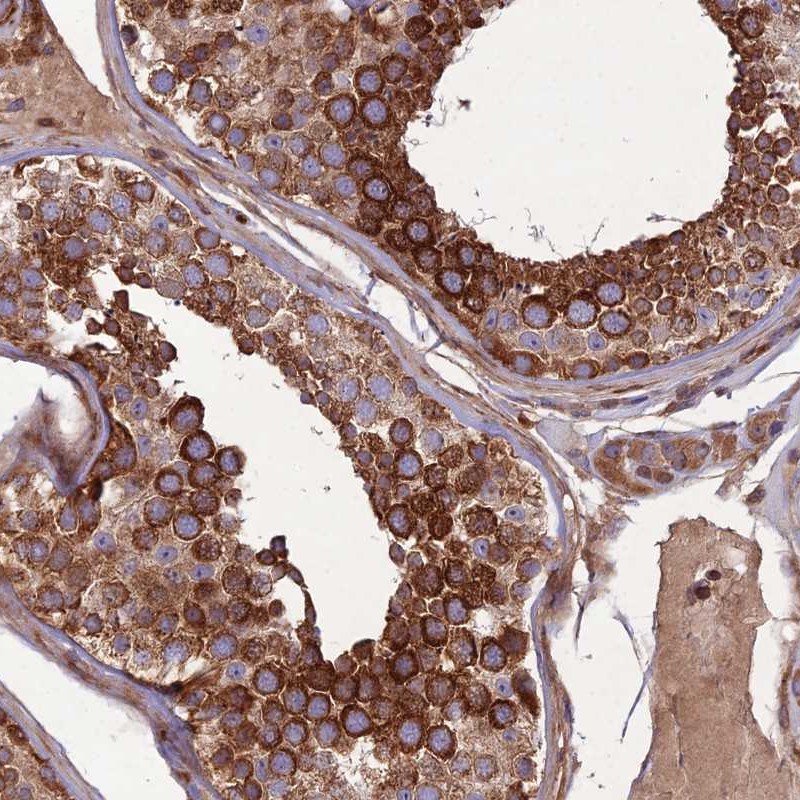

Immunohistochemical staining of human testis shows strong cytoplasmic positivity in cells in seminiferus ducts.